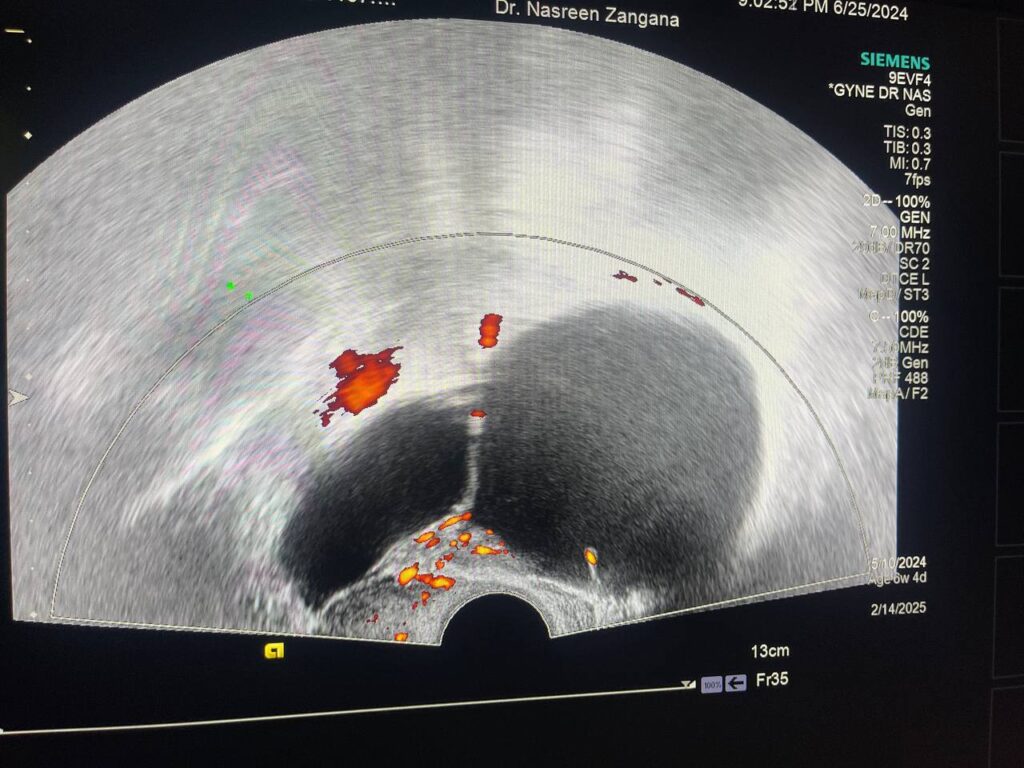

Left adnexal multilocular (< 10) cystic mass > 119x70mm, no extension to surrounding tissue, no ascites, no lymph node, mostly benign, for further study, low grade tumor cannot be excluded